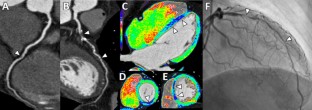

Fig. 1